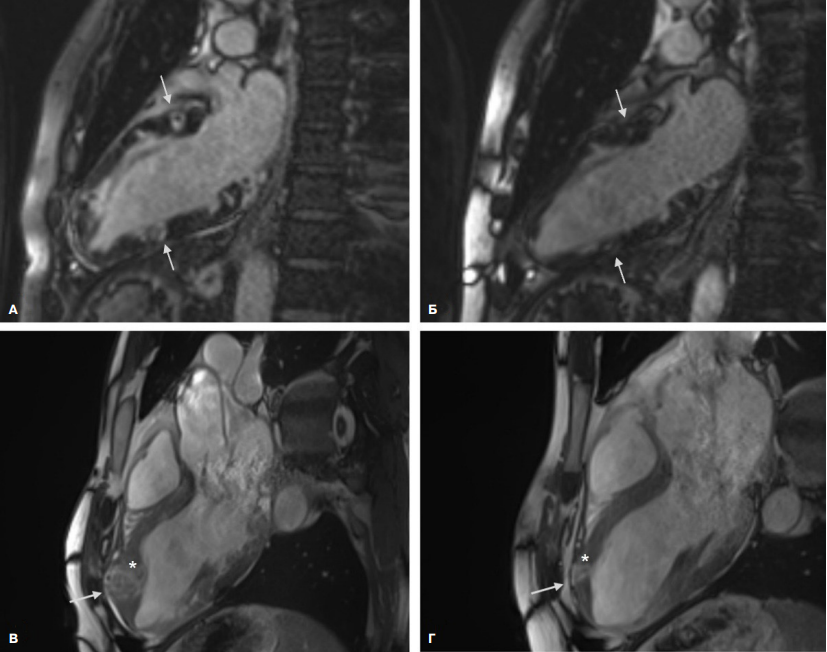

По решению онкоконсилиума пациенту была назначена комбинированная иммунотерапия (ниволумаб + ипилимумаб). При выписке также назначена антикоагулянтная терапия (ривароксабан 20 мг), гипотензивная терапия (эналаприл 10 мг, амлодипин 5 мг), бисопролол 5 мг. На фоне иммунотерапии через несколько месяцев была отмечена положительная динамика в виде регресса размеров и количества образований. По данным МРТ сердца через 3 мес. наблюдалось значительное уменьшение метастазов в размерах (размер наибольшего образования в области верхушки ЛЖ составил ~18×11 мм (рис. 3)).

Рис. 3. МРТ сердца: множественные интрамиокардиальные образования до начала иммунотерапии (слева) и после 3 мес. иммунотерапии (справа). А, Б — режим отсроченного контрастирования, двухкамерная проекция; В, Г — кино-режим, трехкамерная проекция. Стрелки указывают на несколько образований в стенках ЛЖ, звездочкой отмечено образование наибольших размеров.